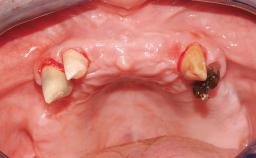

Transition from an “irrational to treat” Maxillary Dentition to a Full-Arch Segmented FDP by Early Loading of Eight Implants Placed Using the Staged Approach

The staged approach permits the transition from an “irrational to treat”dentition to a full arch implant supported restoration without any need to use a removable provisional prosthesis or to apply the immediate-placement and immediate-loading techniques.  A failing dentition is the usual indication for a staged treatment. On the other hand, the dentition should still contain many residual teeth, but with few or none of them being suitable for use as definitive abutments for a full-arch fixed restoration.This situation is usually the result of advanced periodontal disease or of the failure of an extensive fixed prosthesis.

Case Type Edentulous Maxilla

Jaw Maxilla

Area Full-Arch

# of Teeth All

Periodontal Status History of periodontitis or genetic predisposition